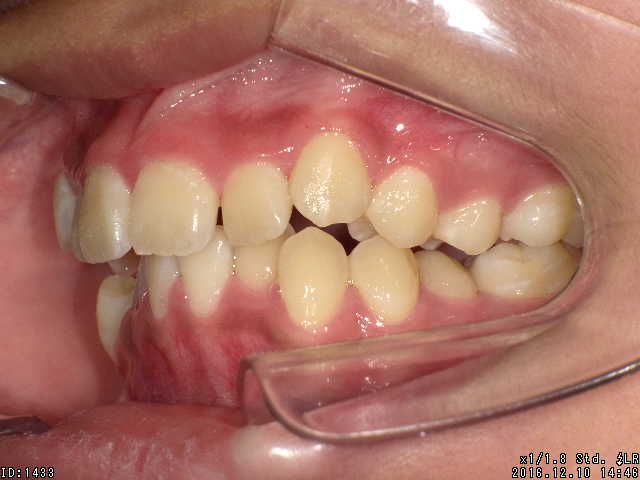

矯正前